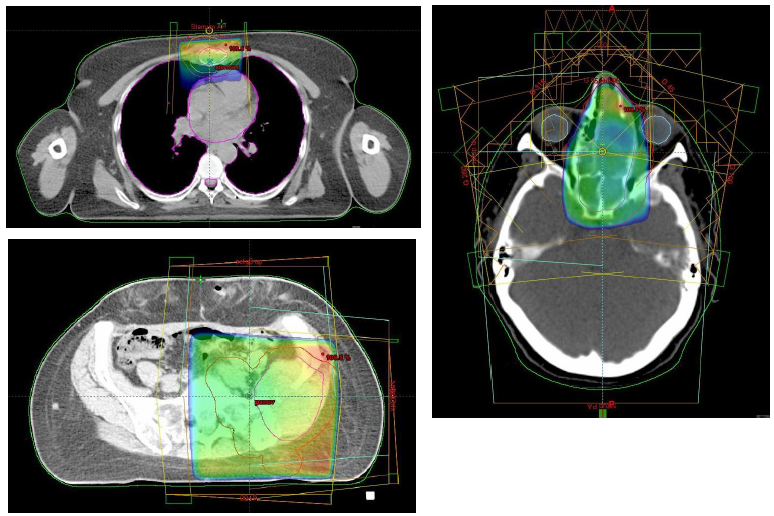

Extrakraniální SBRT/SRS

- U solitárních metastáz či oligometastáz

- Když není vhodná chirurgická metastazektomie

- Nevýhoda(??): chybí histologie z resekátu

- Nutné vybavení pracoviště a zkušenost